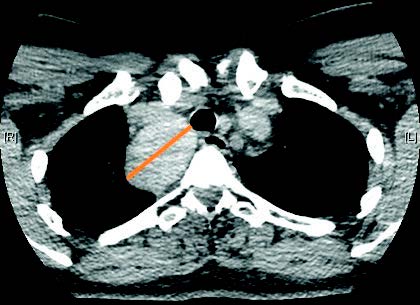

El tipo de intervención realizado ha sido en un 52,5% (N=21) de los casos la tiroidectomía total, en el 25% (N=10) de los casos se realizó una hemitiroidectomía izquierda, el 20% (N=8) hemitiroidectomía derecha y por último, en un 2,5% (N=1) se realizó una resección de un nódulo tiroideo de 4 cm completamente ectópico a la glándula tiroides, con sospecha de posible carcinoma papilar de tiroides, que tras una anatomía patológica intraoperatoria que descarta malignidad, se desestima finalmente la extirpación de la glándula tiroidea.

FIGURA 2